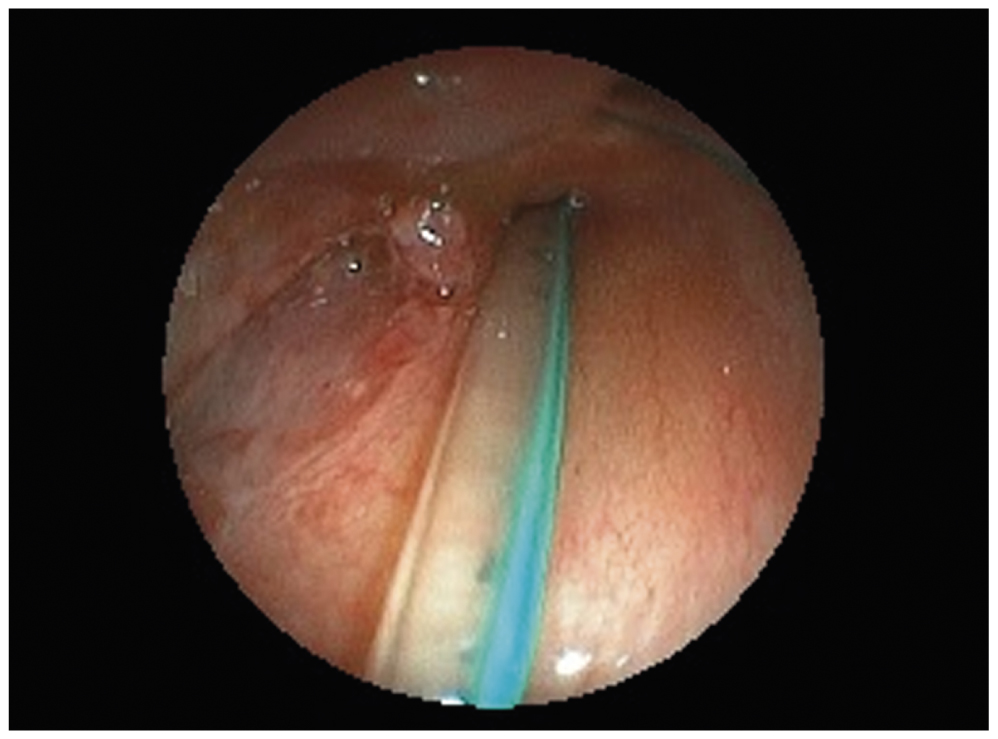

Если задренировать желудок не удавалось, то выполняли фиброэзофагоскопию ультратонким эндоскопом, при которой в ряде случаев возможно было не только оценить локализацию и размеры дефекта стенки пищевода, но и ввести зонд в желудок под эндоскопическим контролем (рис. 6, 7).

Рис. 6. Эзофагоскопия: желудочный зонд установлен через левый грушевидный синус; видна интубационная трубка в просвете гортани

Fig. 6. Esophagoscopy: nasogastric tube has been inserted through the left pyriform sinus (the intubation tube can be seen in the laryngeal lumen)

Рис. 7. Эзофагоскопия: желудочный зонд установлен в просвет пищевода под эндоскопическим контролем; виден дефект в области левого грушевидного синуса

Fig. 7. Esophagoscopy: nasogastric tube has been inserted into the esophageal lumen has been performed under endoscopic guidance. A left pyriform sinus defect is now clearly visible